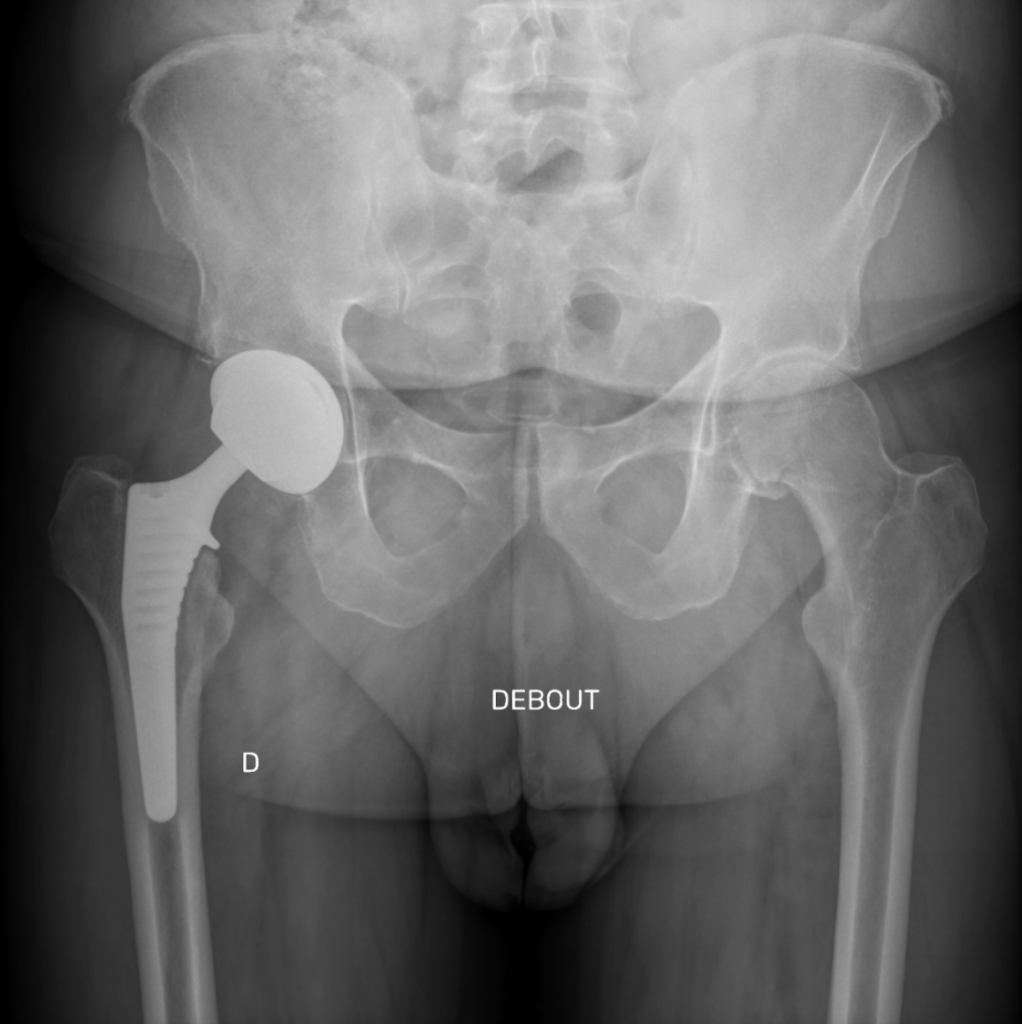

Le diagnostic de la nécessité d’une prothèse de hanche est établi par un examen clinique approfondi, des radiographies et éventuellement d’autres examens d’imagerie. Le Dr Gastaud évaluera votre condition médicale pour déterminer si une prothèse de hanche est appropriée.

1. Inégalité de longueur des jambes

• Comment ce risque est-il minimisé ?

• Une planification informatique préopératoire est réalisée pour anticiper les besoins spécifiques de chaque patient.

• Une analyse peropératoire est effectuée pour ajuster la position pendant la chirurgie, en particulier lors de la voie antérieure, où le patient est positionné sur le dos.

• Pourquoi une inégalité peut-elle encore survenir ?

• Malgré ces précautions, des ajustements de la tige ou des variations dans la posture peuvent entraîner une légère différence de longueur entre les jambes.

• Dans la majorité des cas, cette inégalité est imperceptible pour le patient. Toutefois, dans certains cas, elle peut être ressentie et devenir gênante.